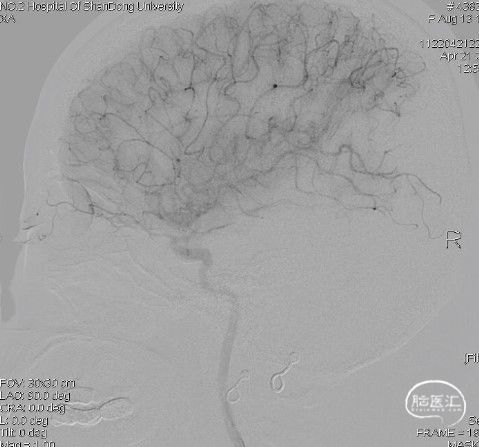

左颈内动脉:大脑前动脉通过前交通动脉向右侧代偿供血,左侧大脑中动脉分叉部分支闭塞。

左侧颈总动脉正位:

左侧颈总动脉侧位: